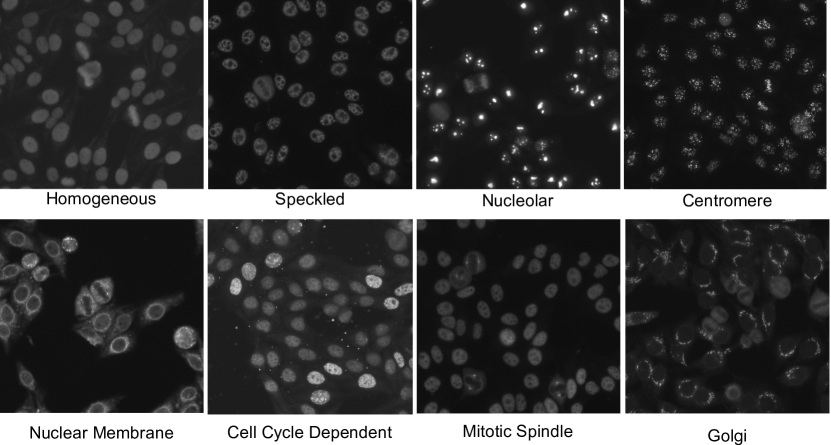

The proposed dataset was obtained from 262 patient sera in 2013. The patient sera were diluted to 1:80 dilution. The prepared specimen was then photographed using a monochrome high dynamic range cooled microscopy camera fitted on a microscope. In total there were 262 specimen images classified into eight classes: homogeneous, speckled, nucleolar, centromere, nuclear membrane (NuMem), cell cycle dependent (CCD), mitotic spindle (MitSp) and golgi aparatus (golgi).

Each specimen image contains a collection of interphase and mitotic cells which are important for the specimen-level classification (refer to Fig. 2). The mitotic cells are the HEp-2 cells undergoing the mitosis phase. In this phase each cell divides itself into two separate individual cells. The mitotic cells are of importance as they produce a set of antigens which are either less concentrated or undetectable in the interphase stage. Due to this fact, experts consider the pattern of both interphase and mitotic cells in classifying an ANA specimen.

We first selected the most frequently appearing cell-level attributes from each pattern. From the selected set, we further excluded the attributes which appear in at least more than four classes. Finally, to name the cell attributes, we presented each cell attribute to the domain experts who were trained to read ANA by showing them both images classified as positive and negative by the attribute classifier. We note that we presented the cell images in green colour which is similar to the colour of an ANA specimen under a fluorescent microscope. Since the attributes are extracted from each cell region, we could ask more specific questions to the experts in relation to each region (e.g. Please describe the property appearing at the cell boundary). The experts could opt not to name an attribute if they were not able to find any consistent property in the positive cell images. Fig. 5 and 1 present some examples of cell attributes successfully identified by the experts.